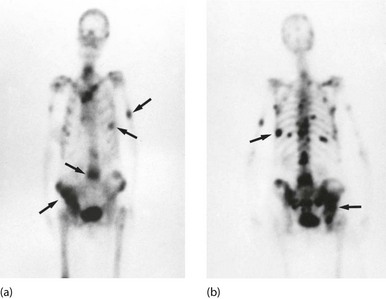

Fig. 5.13 Isotope bone scans

(a) Anterior view of bone scan in a patient with multiple bony metastases (arrowed) from breast cancer. (b) Posterior view of bone scan in the same patient